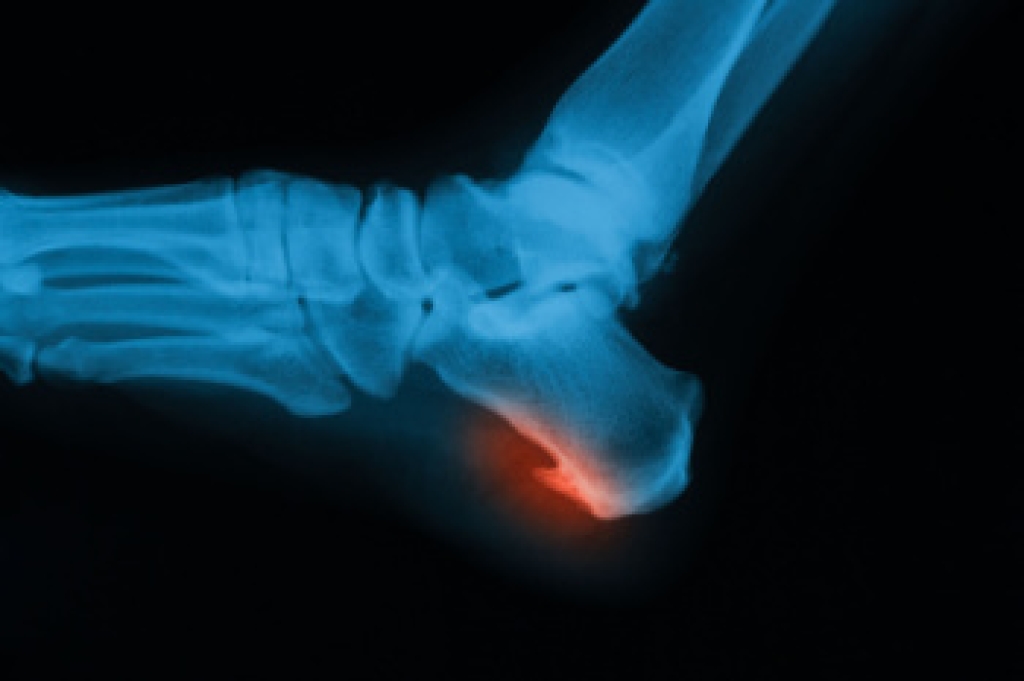

Types of Bone Spurs in the Feet

Bone spurs in the feet, also called osteophytes, form when the body produces extra calcium in response to stress, friction, or inflammation. These growths are not always painful, but they can interfere with nearby tissues and cause discomfort. Heel spurs are one of the most common types. They develop beneath the heel bone from strain on the plantar fascia or at the back of the heel due to tension from the Achilles tendon. Tarsal spurs occur in the midfoot, either on the top or bottom, and often make wearing shoes painful because of pressure against the spur. Toe joint spurs typically affect the big toe, leading to stiffness, limited motion, and pain while walking, especially when arthritis is present. A podiatrist can determine the cause of the bone spur, relieve pressure on surrounding structures, and recommend treatment. If you are experiencing foot or heel pain, it is suggested that you schedule an appointment with a podiatrist for an exam and appropriate treatment.

To figure out the cause of foot pain, podiatrists utilize several different methods. This can range from simple visual inspections and sensation tests to X-rays and MRI scans. Prior medical history, family medical history, and any recent physical traumatic events will all be taken into consideration for a proper diagnosis.